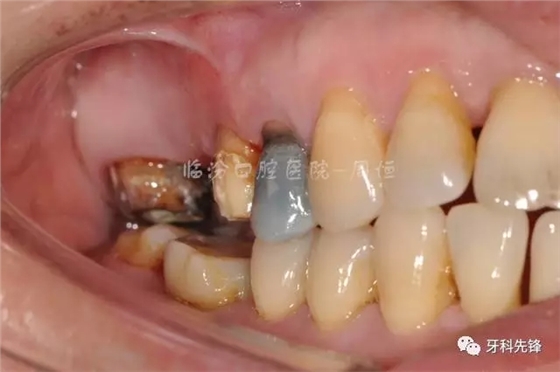

圖4拆除原修復(fù)體牙列照

圖5拆除原修復(fù)體側(cè)位咬合照

圖10冠延長術(shù)后照